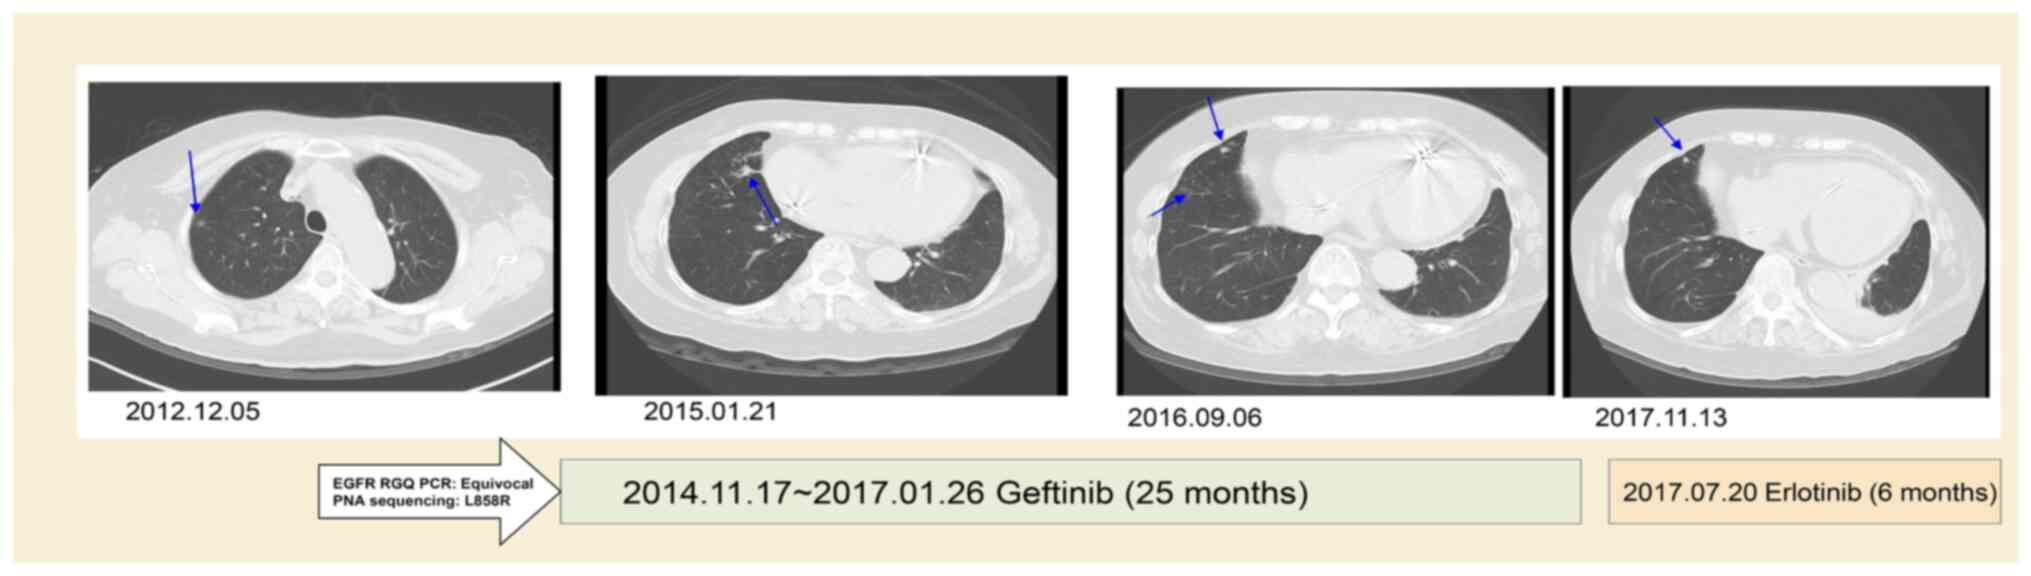

Case 10 was a 78 year female who had stage IIA squamous cell carcinoma (T2aN1M0) and received video-assisted thoracic surgery for the right lower lobe of lung and mediastinal lymph node dissection in 2013. The EGFR RUO kit initially yielded a negative result, with a late upward shifted curve, but was shown to have an EGFR L858R mutation by PNA-sequencing in October 2014. The recurrence of lung cancer with left pleural seeding occurred in November 2014. The patient first received Gefitinib (Iressa; 250 mg OD) treatment for 25 months, which showed mild regression of the left lingual lung. Later, Gefitinib was replaced with Erlotinib (Tarceva; 150 mg OD) for severe xerosis.

The follow-up CT at 31 months after TKI treatment showed a reduction of the right lung tumor of ~53% (from 2.8 to 1.3 cm in diameter) with slight regression of left side pleural seeding (Fig. 2). The patient was lost to follow-up in March 2018.